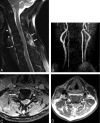

F<sc>ig</sc> 1.

Fig 1.

A 58-year-old man who sustained a unilateral interfacetal dislocation at C5–C6 without SCI. A, Sagittal T2-weighted fast spin-echo (FSE) image (TR/TE/ETL: 2000/80/8) shows an injured disk at C5–C6 with increased signal intensity in the disk and probably avulsion of the anterior longitudinal ligament (dashed arrow). Prevertebral edema (arrowheads) and edema in the posterior paraspinal musculature (white arrows) are present. B, Nonvisualization of the right vertebral artery. MIP image (anterior view) from a 2D time-of-flight acquisition (TR/TE/flip: 40/8.7/30) shows absence of signal intensity in the expected course of the right vertebral artery (dotted line). C, Thrombus in the right foramen transversarium. Axial image from a 3D GRE acquisition (TR/TE/flip: 37/min/15) shows an oval area of low signal intensity in the right foramen transversarium corresponding to thrombus in the right vertebral artery. Note the normal flow-related enhancement in the left foramen transversarium. D, Thombus in the right vertebral artery. Axial FSE image (TR/TE/ETL: 3000/28/4) obtained at a similar level to image in panel C shows a high-signal-intensity thrombus (arrow) in the right foramen transversarium indicative of a thrombosed vertebral artery. Note the normal flow void of the left vertebral artery in the left foramen transversarium.